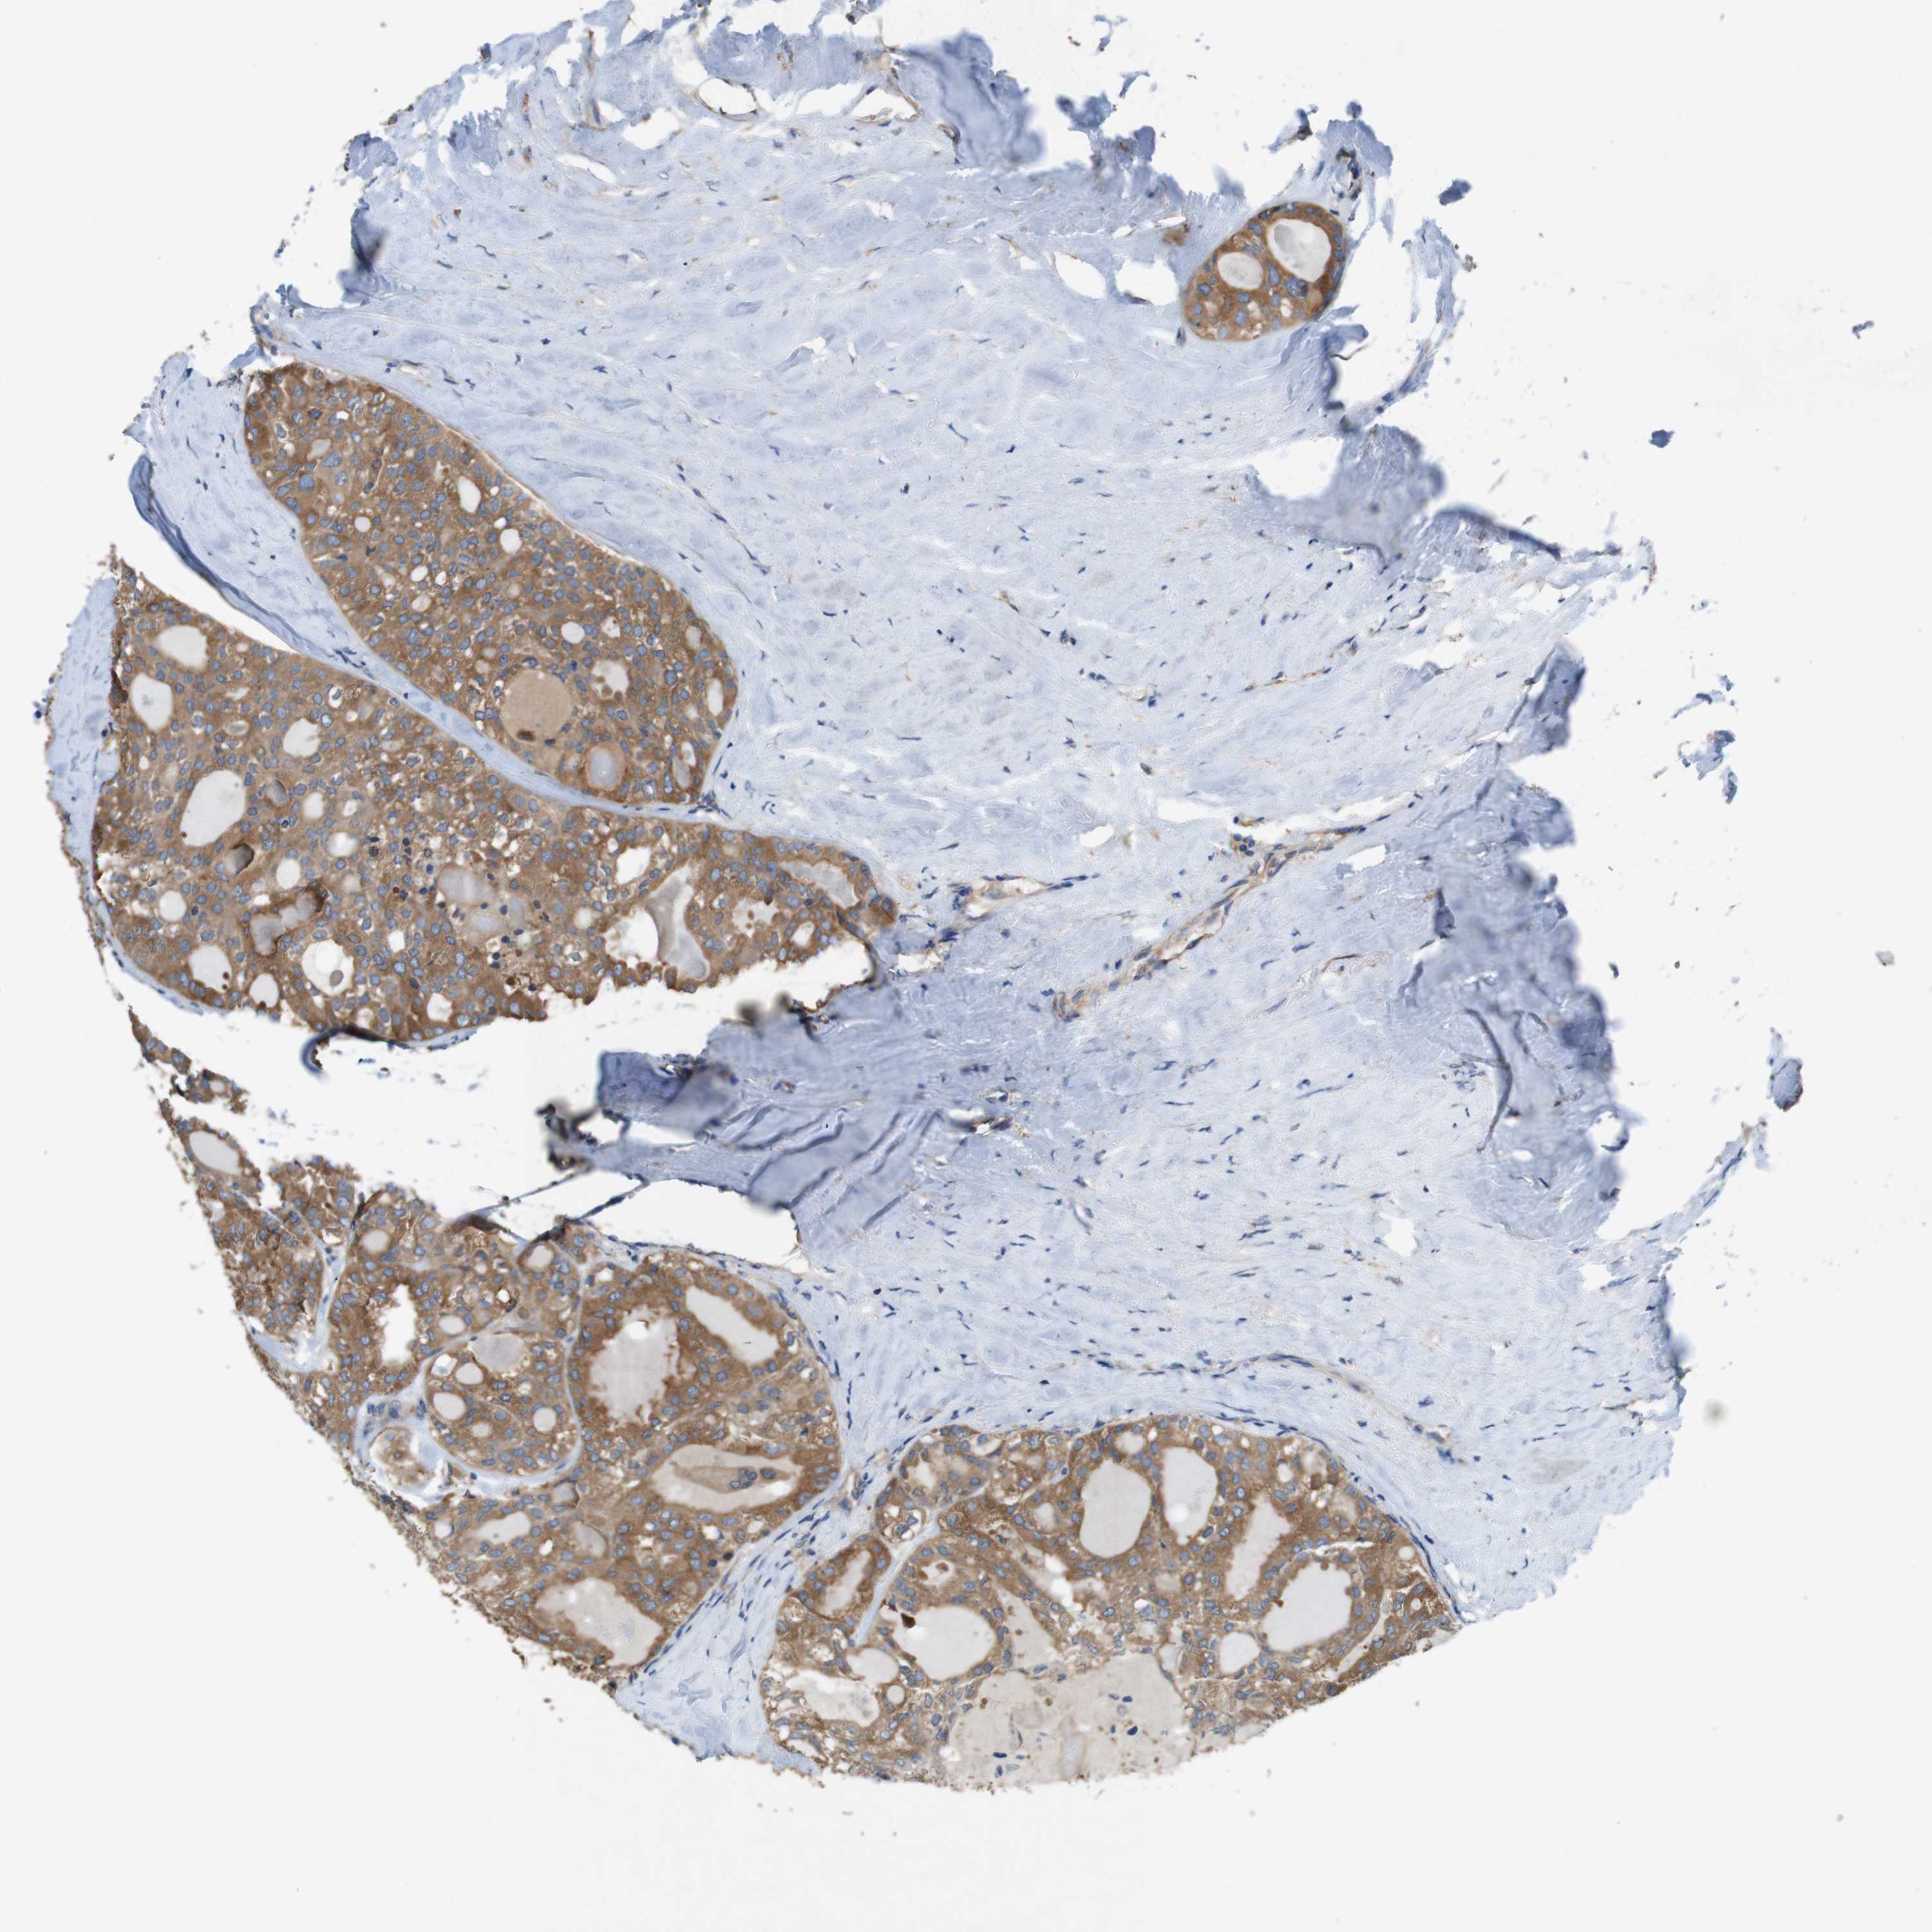

THYROID CANCER - Protein expressioni

A mouse-over function shows sample information and annotation data. Click on an image to view it in a full screen mode. Samples can be filtered based on level of antibody staining by selecting one or several of the following categories: high, medium, low and not detected. The assay and annotation is described here.

Note that samples used for immunohistochemistry by the Human Protein Atlas do not correspond to samples in the TCGA dataset.

Antibody stainingi

Antibody staining in the annotated cell types in the current human tissue is reported as not detected, low, medium, or high, based on conventional immunohistochemistry profiling in selected tissues. This score is based on the combination of the staining intensity and fraction of stained cells.

Each image is clickable and will lead to virtual microscopy that enables deeper exploration of all samples and also displays staining intensity scores, fraction scores and subcellular localization as well as patient and tissue information for each sample.

Antibody HPA034635

Antibody CAB009108

Staining

High

Medium

Low

Not detected

Intensity

Strong

Moderate

Weak

Negative

Quantity

>75%

75%-25%

<25%

None

Location

Nuclear

Cytoplasmic/membranous

Cytoplasmic/membranous,nuclear

Papillary adenocarcinoma, NOS

Follicular adenoma carcinoma, NOS